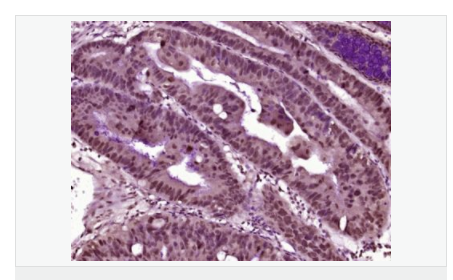

image.png